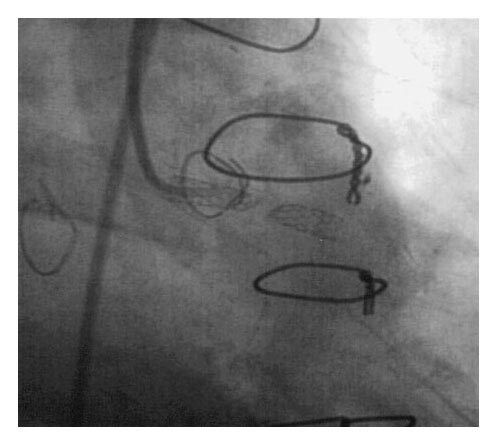

A 57-year-old man presented with several hours of chest discomfort accompanied by ischemic changes on electrocardiography, consistent with an acute coronary syndrome (ACS). His medical history was notable for CABG performed one year earlier, followed by PCI with stent deployment in an SVG supplying the first obtuse marginal artery. Coronary angiography revealed severe three-vessel disease of the native coronary arteries, a patent left internal thoracic artery (LITA) graft to the left anterior descending (LAD) artery, a chronically occluded vein graft to the right coronary artery (RCA), and a newly occluded SVG to the first obtuse marginal artery.

This angiographic pattern reflects the well-recognized disparity in long-term patency between arterial and venous bypass conduits.